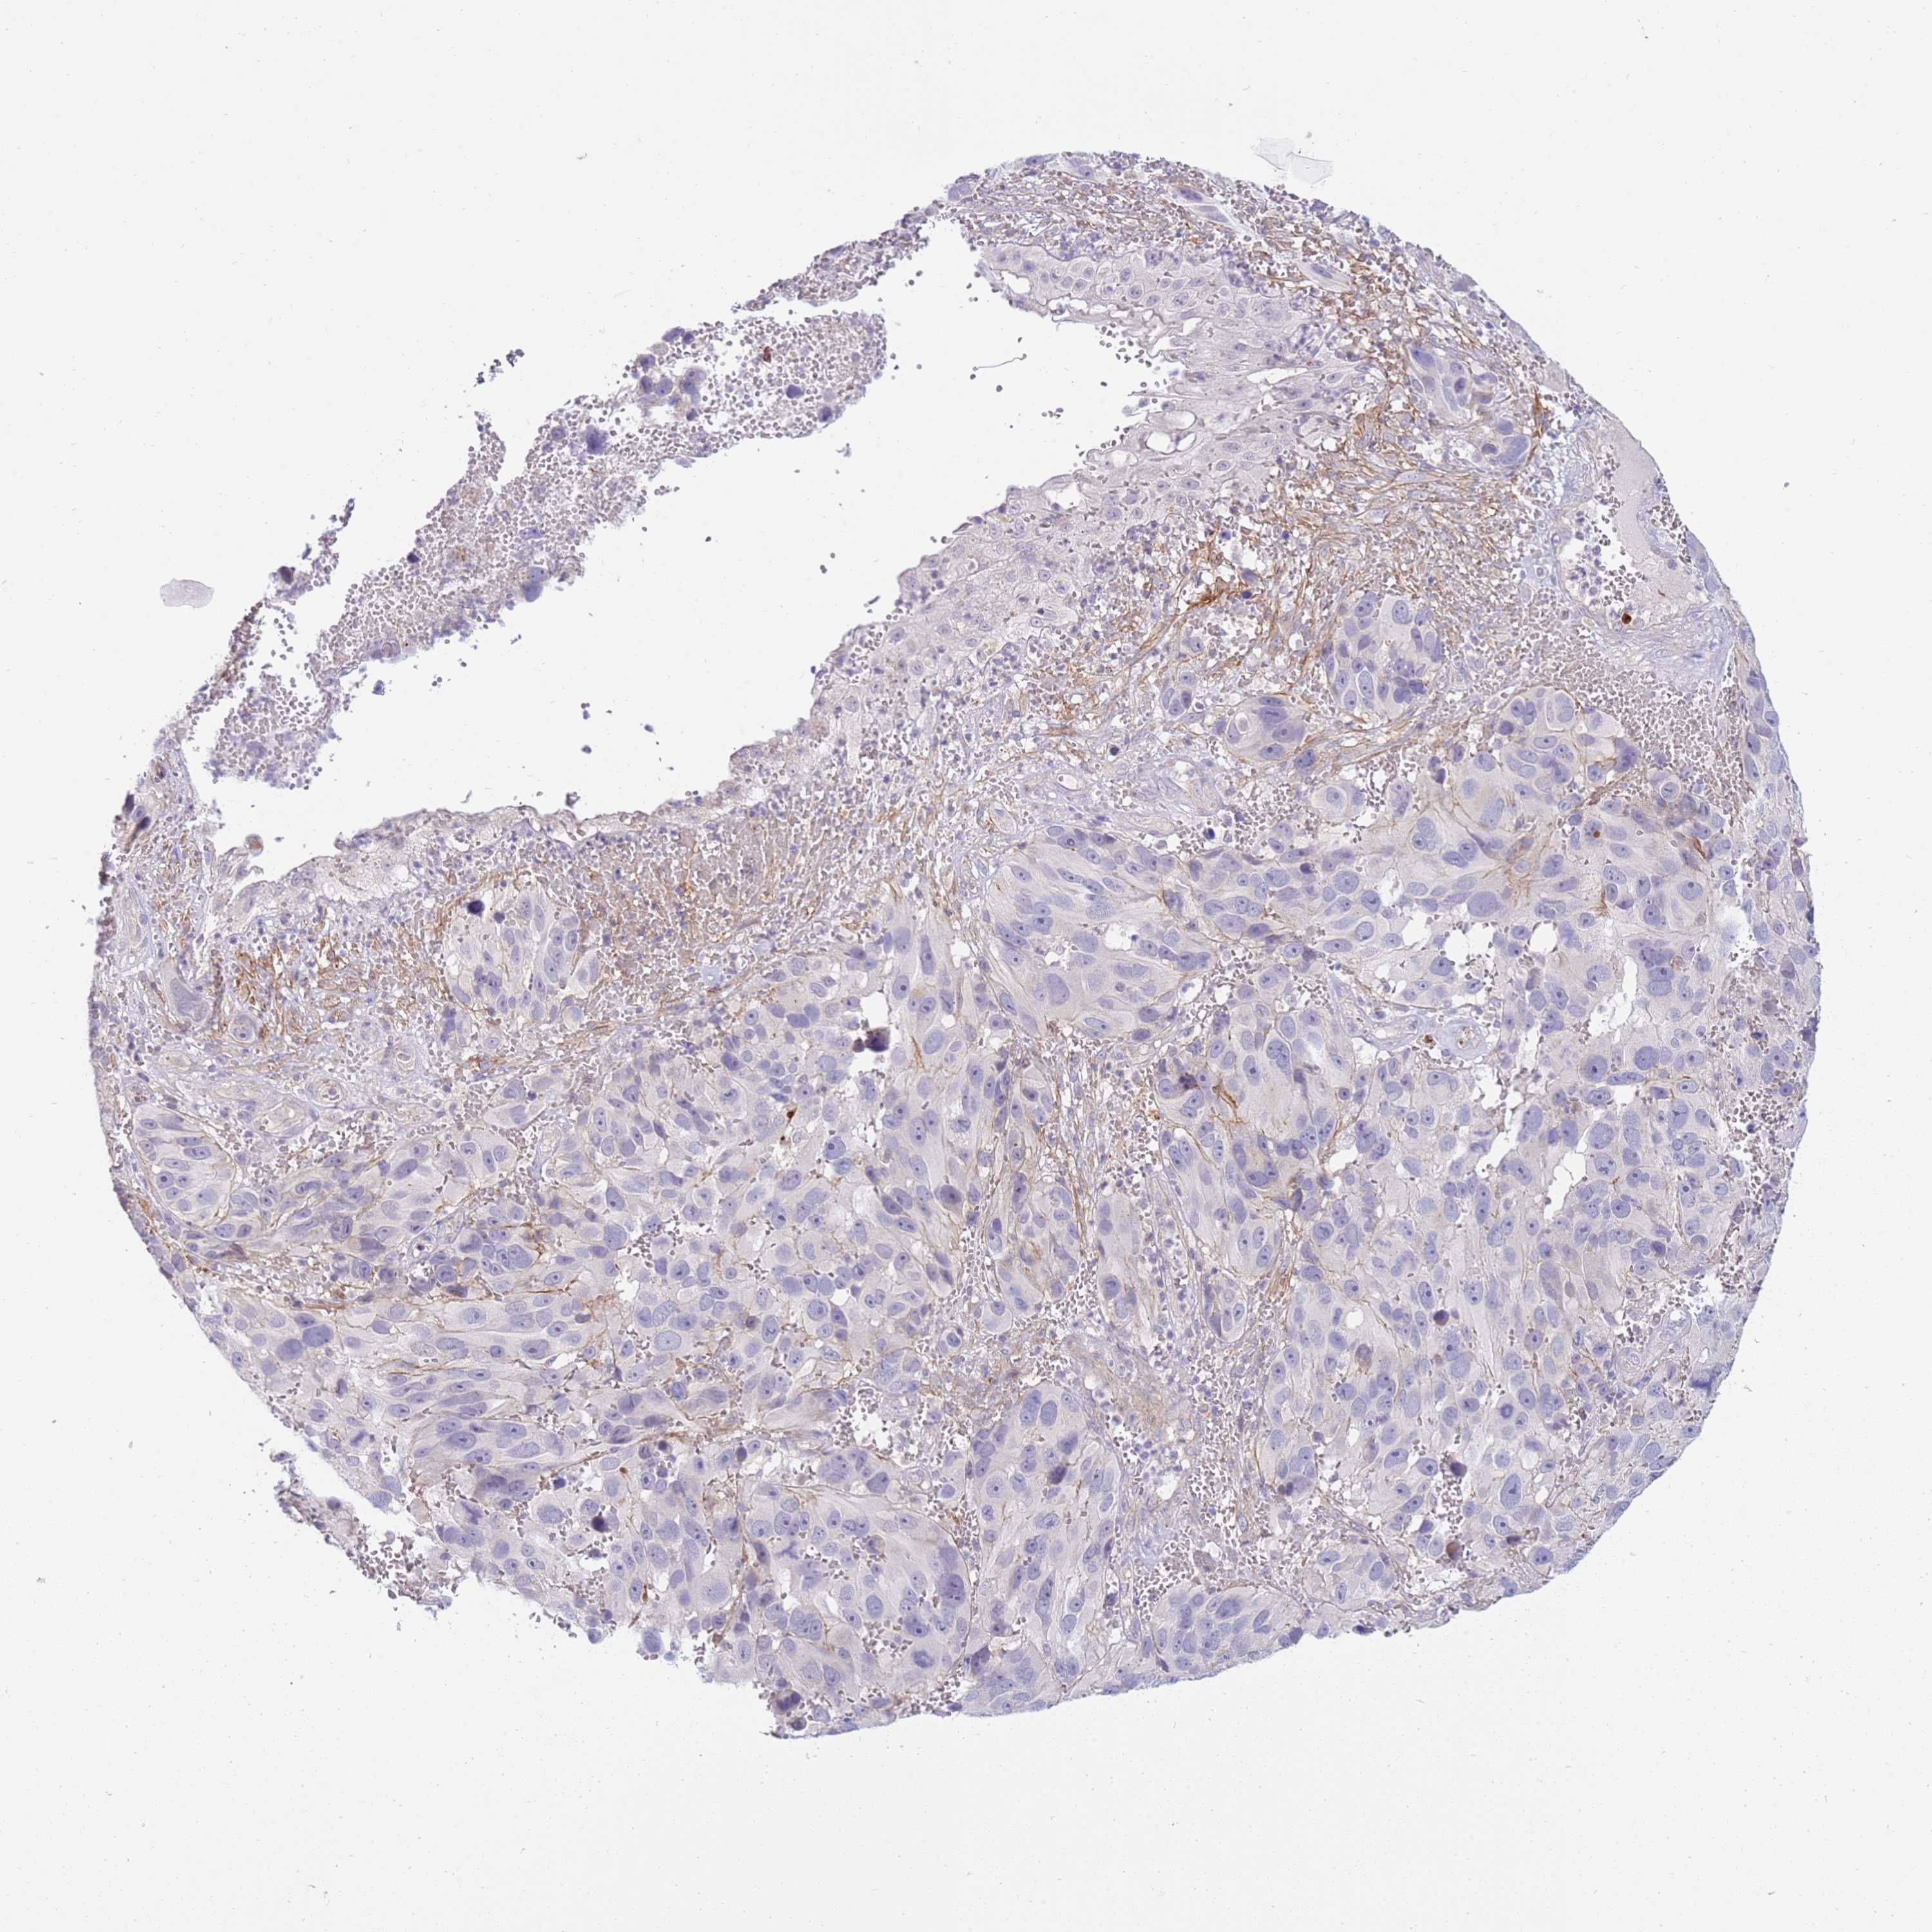

MELANOMA - Protein expressioni

A mouse-over function shows sample information and annotation data. Click on an image to view it in a full screen mode. Samples can be filtered based on level of antibody staining by selecting one or several of the following categories: high, medium, low and not detected. The assay and annotation is described here.

Note that samples used for immunohistochemistry by the Human Protein Atlas do not correspond to samples in the TCGA dataset.

Antibody stainingi

Antibody staining in the annotated cell types in the current human tissue is reported as not detected, low, medium, or high, based on conventional immunohistochemistry profiling in selected tissues. This score is based on the combination of the staining intensity and fraction of stained cells.

Each image is clickable and will lead to virtual microscopy that enables deeper exploration of all samples and also displays staining intensity scores, fraction scores and subcellular localization as well as patient and tissue information for each sample.

Antibody HPA047147

Staining

High

Medium

Low

Not detected

Intensity

Strong

Moderate

Weak

Negative

Quantity

>75%

75%-25%

<25%

None

Location

Nuclear

Cytoplasmic/membranous

Cytoplasmic/membranous,nuclear

Malignant melanoma, NOS

Malignant melanoma, Metastatic site